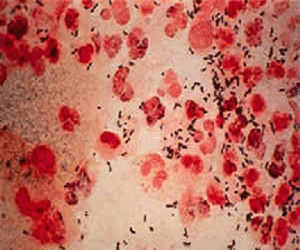

淋病

淋菌性阴道炎